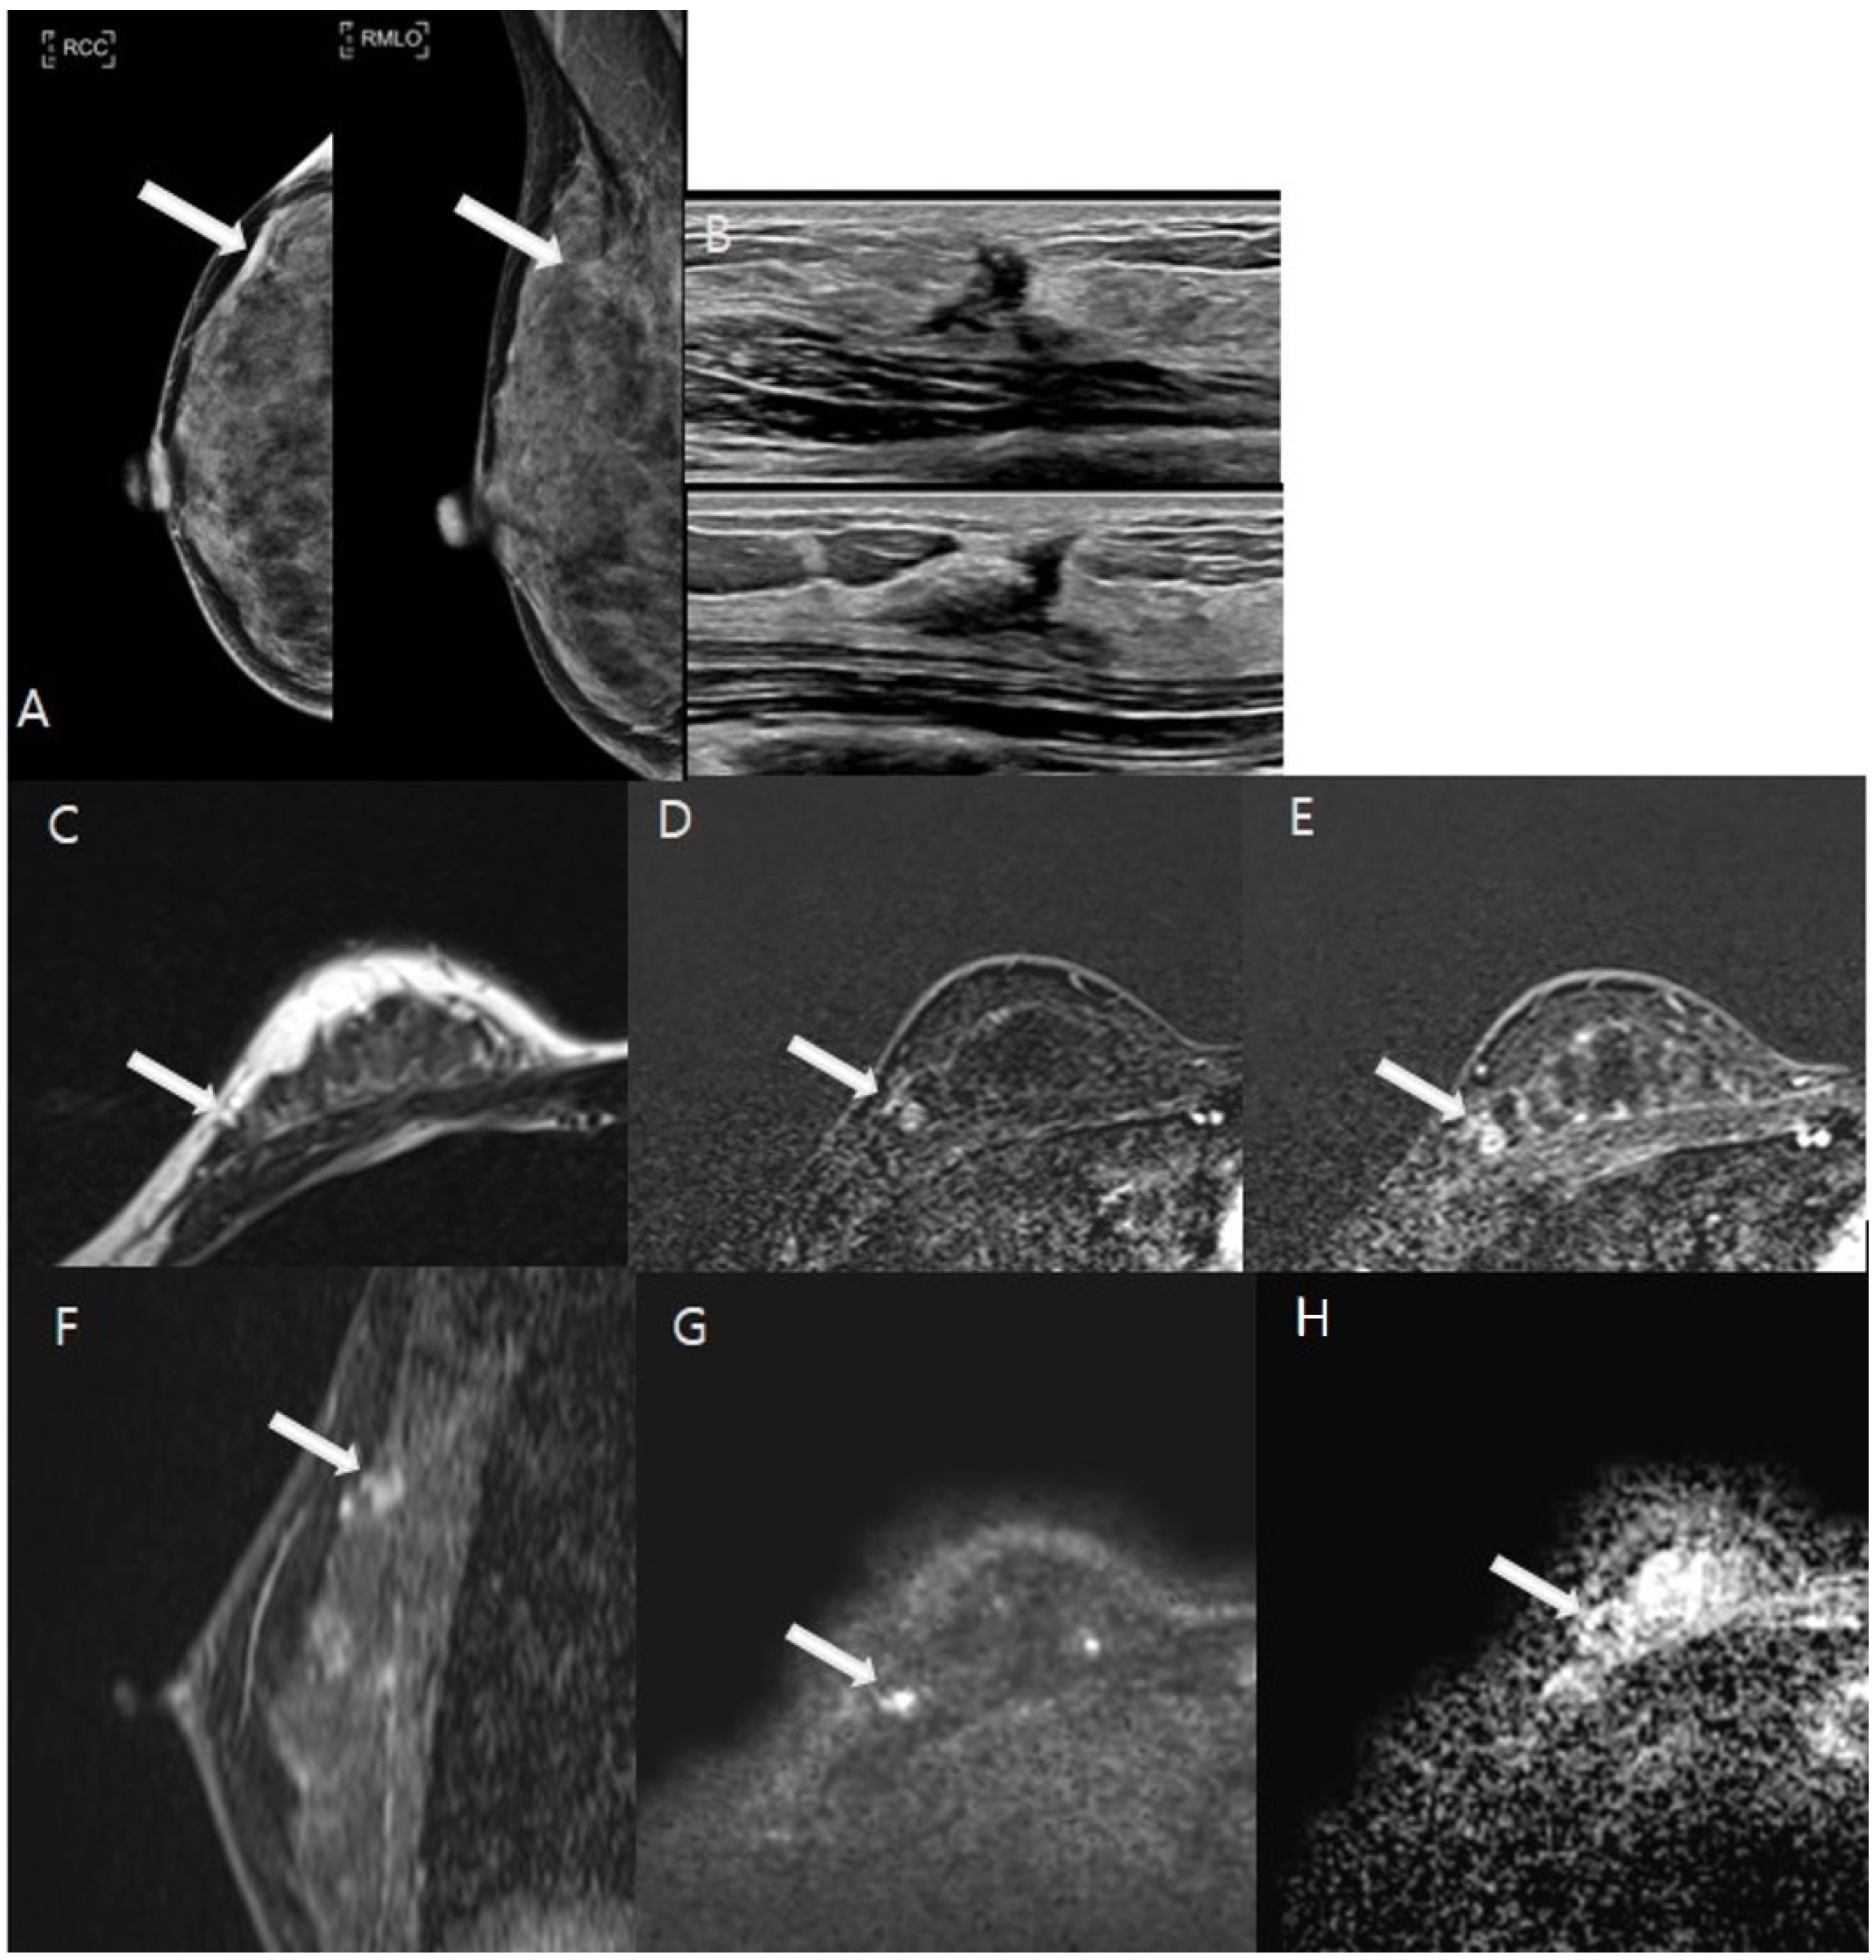

3.2. Image Analysis Results

3.3. The Diagnostic Performance of the Imaging Modalities